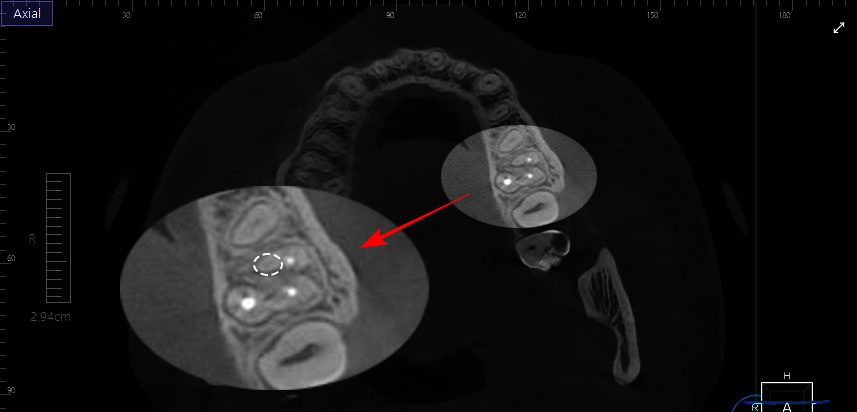

당산동 치과 에서 준비한 CBCT 자료를 보시면

하얗게 재료가 충전되어 있는 세 개의 근관 사이로

둥근 형태의 구조가 보이실 겁니다.

이 부분이 숨겨져 있던 MB2라 의심해 볼 수 있습니다.

본래 내부 통로가 투과되어 선명하게 관찰되는데

내부가 통로가 일절 보이지 않죠.

이런 경우, 석회화를 의심해 볼 수 있습니다.

당산동 치과 에서 준비한 자료를 보시면

어금니 내부가 매우 크고 자세하게 보이죠.

미세현미경을 활용했기 때문이랍니다.

사진 속 세 개의 근관이 잘 보이죠?

저는 그 사이에 있는 MB2근관의 흔적이 눈에 들어옵니다.

작은 원형 통로가 보이는데,

이 부분을 미세한 기구로 긁어내다 보면

입구를 찾을 수 있습니다.

당산동 치과 에서 표시한 부분을 보시면

흔적만 있던 부분을 더 긁어내 MB2 입구가

명확히 보이고 있습니다.

미세현미경을 사용했기 때문에 흔적을 찾아

입구까지 도달하기 비교적 수월했던 것이죠.